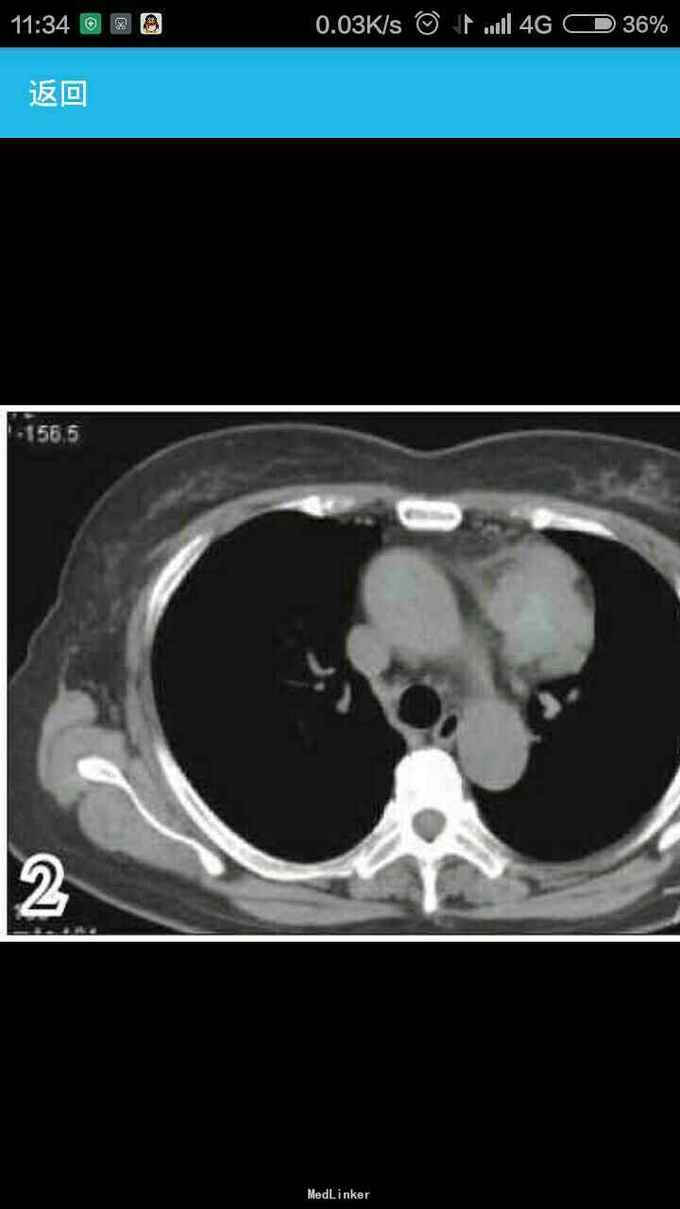

女性,60岁,因左 趾关节红肿、剧痛,红肿弥漫足背 23天来诊,不伴发热,无外伤史, 全身体检无明显异常。 胸片示,左侧前上纵隔占位性病变(图1)。胸部CT示,左侧前上纵隔内见5.7 cm×3.8 cm软组织肿块影,内见斑片状稍高密度影,境界不清(图2——5)。 实验室检查显示,血尿酸517.1 μmol/L(正常值180——357 μmol/L),临床诊断为“急性痛风”,为排除相关疾病作进一步检查。 印象:左侧前上纵隔占位(恶性肿瘤?畸胎瘤?)。 手术结果:肿瘤位于左前纵隔,大小约为8 cm×8 cm ×6 cm,质硬,表面光滑,与心包、无名静脉、肺门粘连(侵犯壁层、脏层、胸膜、肺门、心包、膈肌、膈神经,伴肿大淋巴结)。【病理结果示】(图6):肿块9 cm×6 cm×4 cm,侵犯周围脂肪组织,伴神经内分泌分化。肿块标记:CD5(+)、CD117(+)、嗜铬粒蛋白A(CgA)灶(+)、突触素(Syn,+)、CD56 (-)、细胞增殖因子Ki-67约20%(+)。【诊断】胸腺鳞状细胞癌Ⅱ——Ⅲ级,伴神经内分泌分化。